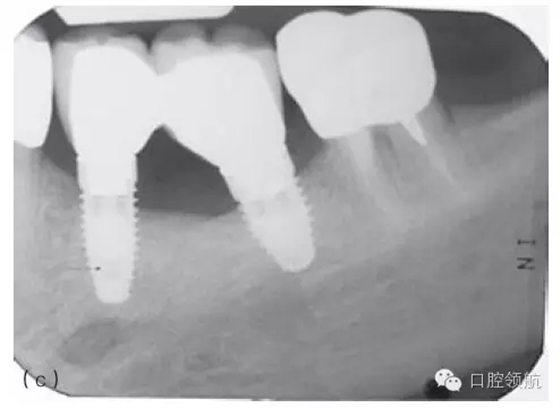

因種植體裝置界面的扭矩可能會使平臺連接出現(xiàn)潛在的變形,故應注意使該扭矩最小化。Ⅳ類骨植入種植體時要優(yōu)先在骨上敲打擠壓而不是依靠種植體來擠壓骨洞。許多廠家會提醒不要超過手術操作時推薦的扭矩,以減小折斷的可能性(圖5.3a~c)。

圖5.3 (a)Ⅰ類骨中的種植體內連接和界面破損的影像學表現(xiàn)。(b)取出種植體,發(fā)現(xiàn)沿著種植體平臺的損壞。(c)在重新放置的種植體上行聯(lián)冠修復完成2年后的影像學表現(xiàn)。